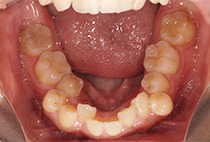

出っ歯と前歯のガタつきにお悩みだった20代女性の症例です。

金属アレルギーがあるため、メタルフリーで治療できる【インビザライン】による抜歯矯正を選択されました。

前歯のガタガタ、中心のずれ、顎のずれ、外科矯正は避けたい

叢生、左右非対称咬合